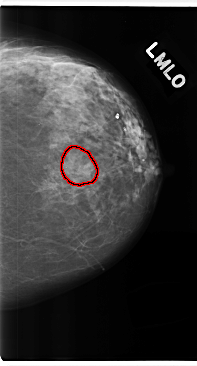

FILE: C_0226_1.LEFT_MLO.OVERLAY

TOTAL_ABNORMALITIES 1

ABNORMALITY 1

LESION_TYPE CALCIFICATION TYPE AMORPHOUS DISTRIBUTION CLUSTERED

ASSESSMENT 3

SUBTLETY 3

PATHOLOGY BENIGN

TOTAL_OUTLINES 1

BOUNDARY